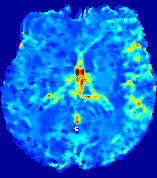

LesionRefer to captionRefer to captionRefer to captionRefer to captionRefer to captionRefer to caption𝐕rgbsubscript𝐕𝑟𝑔𝑏{\bf{V}}_{rgb}Refer to captionRefer to captionRefer to captionRefer to captionRefer to captionRefer to caption𝐕2subscriptnorm𝐕2{\|\bf{V}}\|_{2}Refer to captionRefer to captionRefer to captionRefer to captionRefer to captionRefer to captionRefer to caption3.53.53.52.82.82.82.12.12.11.41.41.40.70.70.70.00.00.0(mm/s)𝑚𝑚𝑠(mm/s)D𝐷DRefer to captionRefer to captionRefer to captionRefer to captionRefer to captionRefer to captionRefer to caption0.0200.0200.0200.0160.0160.0160.0120.0120.0120.0080.0080.0080.0040.0040.0040.0000.0000.000(mm2/s)𝑚superscript𝑚2𝑠(mm^{2}/s)Slice #1Slice #2Slice #3Slice #4Slice #5Slice #6

Figure 4: PIANO feature maps for another patient in the ISLES 2017 training set, where the lesion is located in the right hemisphere. Top row: segmented stroke lesion region (white) on different slices. The corresponding slices for the PIANO feature maps are shown in the following rows.

For a better insight into an estimated velocity field 𝐕𝐕{\bf{V}} and diffusion field 𝐃𝐃{\bf{D}}, we compute the following maps: (1) 𝐕rgbsubscript𝐕𝑟𝑔𝑏{\bf{V}}_{rgb}: Color-coded orientation map of 𝐕=(Vx,Vy,Vz)T𝐕superscriptsuperscript𝑉𝑥superscript𝑉𝑦superscript𝑉𝑧𝑇{\bf{V}}=(V^{x},V^{y},V^{z})^{T}, obtained by normalizing 𝐕𝐕{\bf{V}} to unit length and mapping its 3 components to red, green, blue respectively; (2) 𝐕2subscriptnorm𝐕2\|{\bf{V}}\|_{2}: 222 norm of 𝐕𝐕{\bf{V}}; (3) D𝐷D: scalar field in Eq. 5.

Fig. 3 and Fig. 4 show the PIANO feature maps estimated from two ISLES 2017 patients: all are highly consistent with the lesion in both cases. Details of the blood flow trajectories are revealed in 𝐕rgbsubscript𝐕𝑟𝑔𝑏{\bf{V}}_{rgb} by the ridged patterns and the sharp changes of colors in the unaffected (right) hemisphere, while the flat patterns appearing within the lesion provide little directional information about the velocity and indicate low velocity magnitudes. Velocity magnitudes are more directly visualized via 𝐕2subscriptnorm𝐕2\|{\bf{V}}\|_{2}, from which one can easily locate the lesion where 𝐕2subscriptnorm𝐕2\|{\bf{V}}\|_{2} is low. D𝐷D also indicates lower diffusion values in the lesion, though with less contrast potentially due to the fact that it captures the accumulated effect of CA diffusion at the voxel-level.